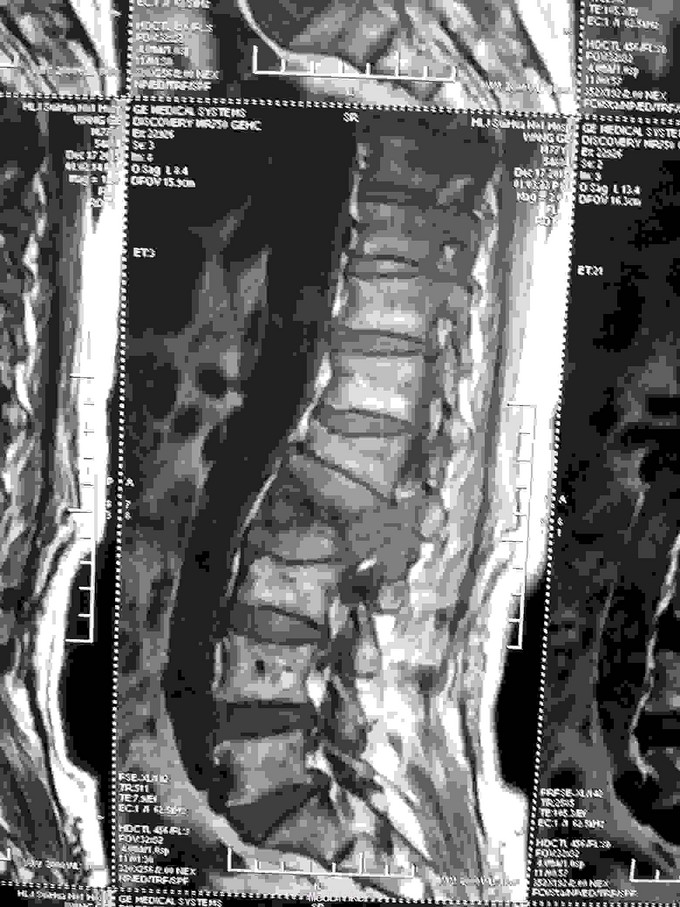

患者老年男性,77岁。因:腰痛,伴双下肢放射痛。活动受限二天。来诊。病人近半年间断腰痛,休息减轻。劳累加重。近二日腰背部疼痛明显加重。不能平卧于床。行走困难。双下肢放射痛。急来诊。因不能平卧,无法查核磁共振,门诊以:腰间盘突出收入院。

查体:神志清,语言流利。呼吸平稳。腹软,腰背部外形较好,无畸形。不能平卧,屈伸活动受限。床上取侧身蜷腿弯腰卧位。双侧下肢放射痛。肌力减退。皮肤感觉麻木。无辅助检查。

根据病史查体诊断:腰间盘突出症待确诊。应用消肿营养神经镇痛治疗。一天。查核磁共振示:腰椎多节段间盘突出伴椎管狭窄。第二腰椎骨破坏侵及椎板。部分突入椎管,脊髓受压。诊断:腰间盘突出伴椎管狭窄。第二腰椎转移癌,脊髓受压。经与家属沟通,查双肺CT:双肺下叶炎症。肺部纤维化。可见肿瘤阴影。肋骨及胸膜受累。胸椎部分骨破坏。最终诊断:双肺癌,胸椎,腰椎骨转移,脊髓受压。多节段腰椎间盘突出。病人至肿瘤科治疗。

该病人以腰痛发病。既往无肿瘤病史。隐匿发病。腰椎骨破坏提示其他部位肿瘤。需进一步详细检查。有时很难发现原发病灶。对此类病人一定注意门诊及病房处置时不要漏诊。